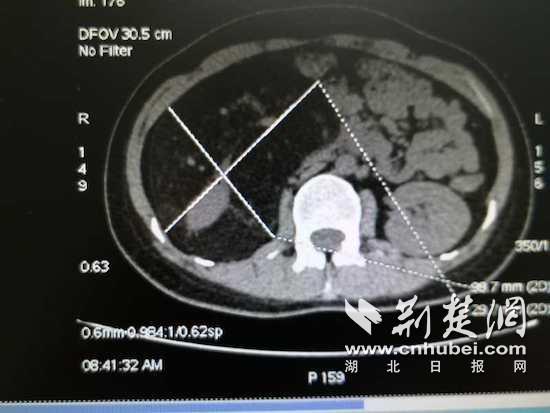

家住光谷的33岁潘女士,近期腹部逐渐隆起。本以为是吃出来的小肚腩,在医院行腹部CT检查后才发现,她的右肾周围有一个22.2*10.1*12.1厘米的肿物,诊断考虑右肾错构瘤可能。医生提醒她赶紧治疗,“否则右肾可能保不住了”。潘女士第一时间赶到家门口的武汉大学人民医院东院区泌尿外科就诊。

“既要完整切除肿瘤,又要保住右肾,相当于要把一棵根系发达的参天巨树连根拔起又不伤及土壤,手术有相当大的难度。”肾错构瘤虽属良性肿瘤,但如此巨大的错构瘤实属罕见。东院泌尿外科主任祝恒成教授接诊后,立即组织全科讨论病情。这个肾错构瘤上达肝脏、下达盆腔,严密包裹右肾。